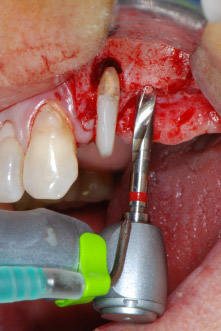

Implant beds were prepared at sites 25 and 26 with rotary instruments, used in a contra-angle handpiece with a 20 : 1 transmission ratio with an updated powerful implant motor (Implantmed, W&H) (Fig. 8).

The final preparation next to the sinus was again carried out with a piezoelectric instrument (Piezomed, insert S2).

Fig. 8: Rotary preparation of the implant bed short of the floor of the maxillary sinus at position 25, carried out with an updated implant motor.